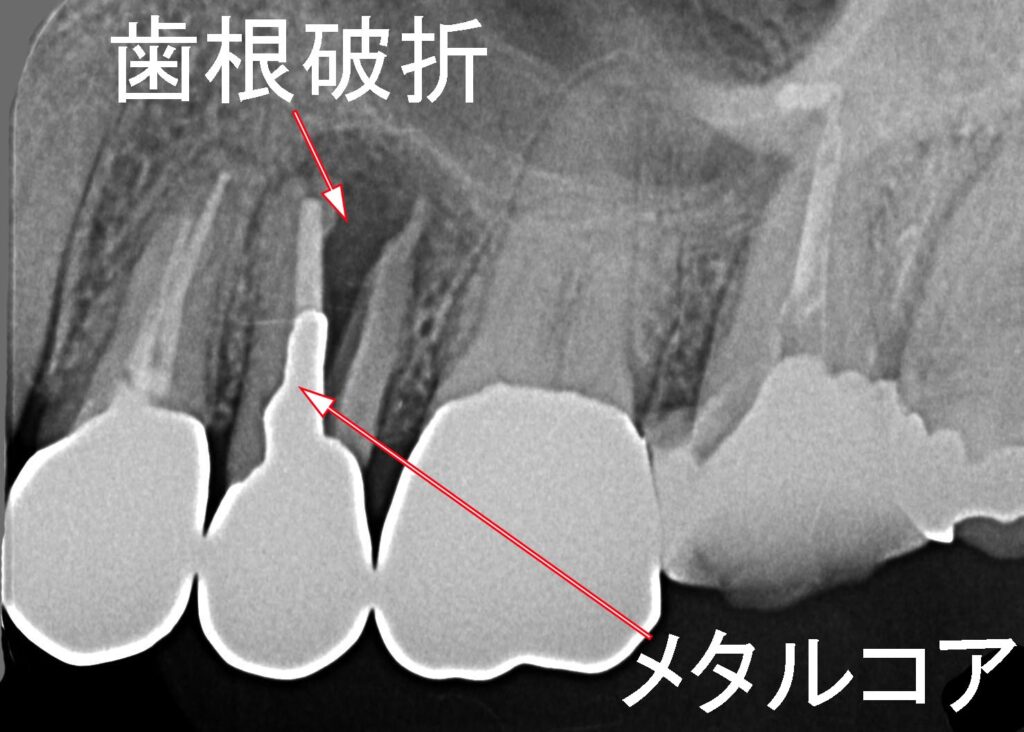

📄上顎第二小臼歯の歯根破折|症例1

- ブリッジの土台になった第二小臼歯が破折。

- メタルコア先端部に応力が集中したことが原因と考えられる。

📄上顎第二小臼歯の歯根破折|症例2

- 歯根が真っ二つに割れ、歯根周囲に炎症と骨吸収(X線で黒く映る)が発生。

- 症例1と同様、メタルコアによる応力集中が原因と推定される。